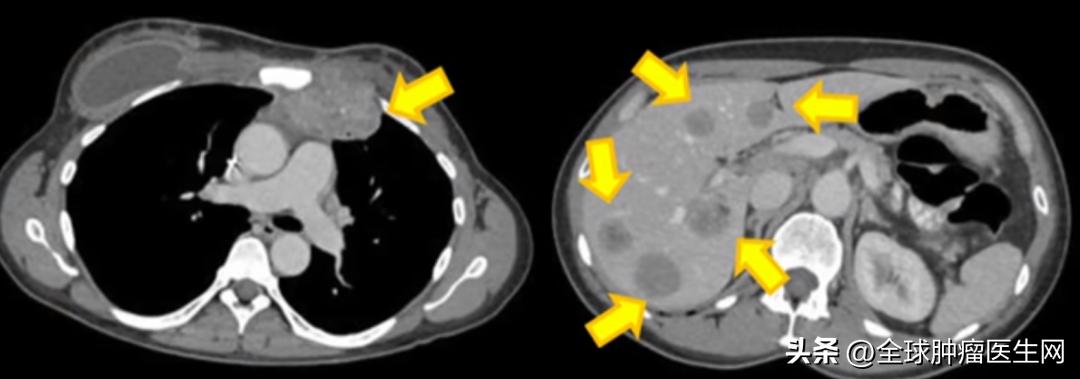

2016年5月,也就是她接受治疗 5个月 后,扫描结果显示肿瘤全部消失,她 没有癌症 了!Rosenberg教授看着影像兴奋的说,这简直是个 “奇迹” 。

患者 4355 TIL 治疗后转移沉积物的消退,左乳房广泛的皮肤损伤已消退。左锁骨上病变(红色圆圈)的消退。患者 4343 原发右乳病变的消退。患者 4331 转移性乳腺癌完全持久消退,评效:CR,完全响应。